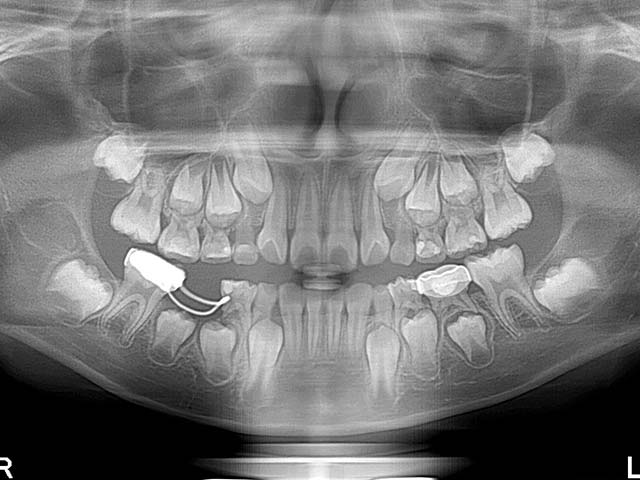

除此之外,兒童拍攝全口X光片還早期發現一些罕見疾病或先天缺牙如下:

1.左下先天性囊腫及缺牙